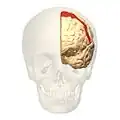

Brodmann area 6 (BA6) is part of the frontal cortex in the human brain. Situated just anterior to the primary motor cortex (BA4), it is composed of the premotor cortex and, medially, the supplementary motor area (SMA). This large area of the frontal cortex is believed to play a role in planning complex, coordinated movements.

Brodmann area 6 is also called agranular frontal area 6 in humans because it lacks an internal granular cortical layer (layer IV). It is a subdivision of the cytoarchitecturally defined precentral region of cerebral cortex. In the human brain, it is located on the portions of the precentral gyrus that are not occupied by Brodmann area 4; furthermore, BA6 extends onto the caudal portions of the superior frontal and middle frontal gyri. It extends from the cingulate sulcus on the medial aspect of the hemisphere to the lateral sulcus on the lateral aspect. It is bounded rostrally by the granular frontal region and caudally by the gigantopyramidal area 4 (Brodmann, 1909).[1]

Image

Lateral view.

Lateral view. -